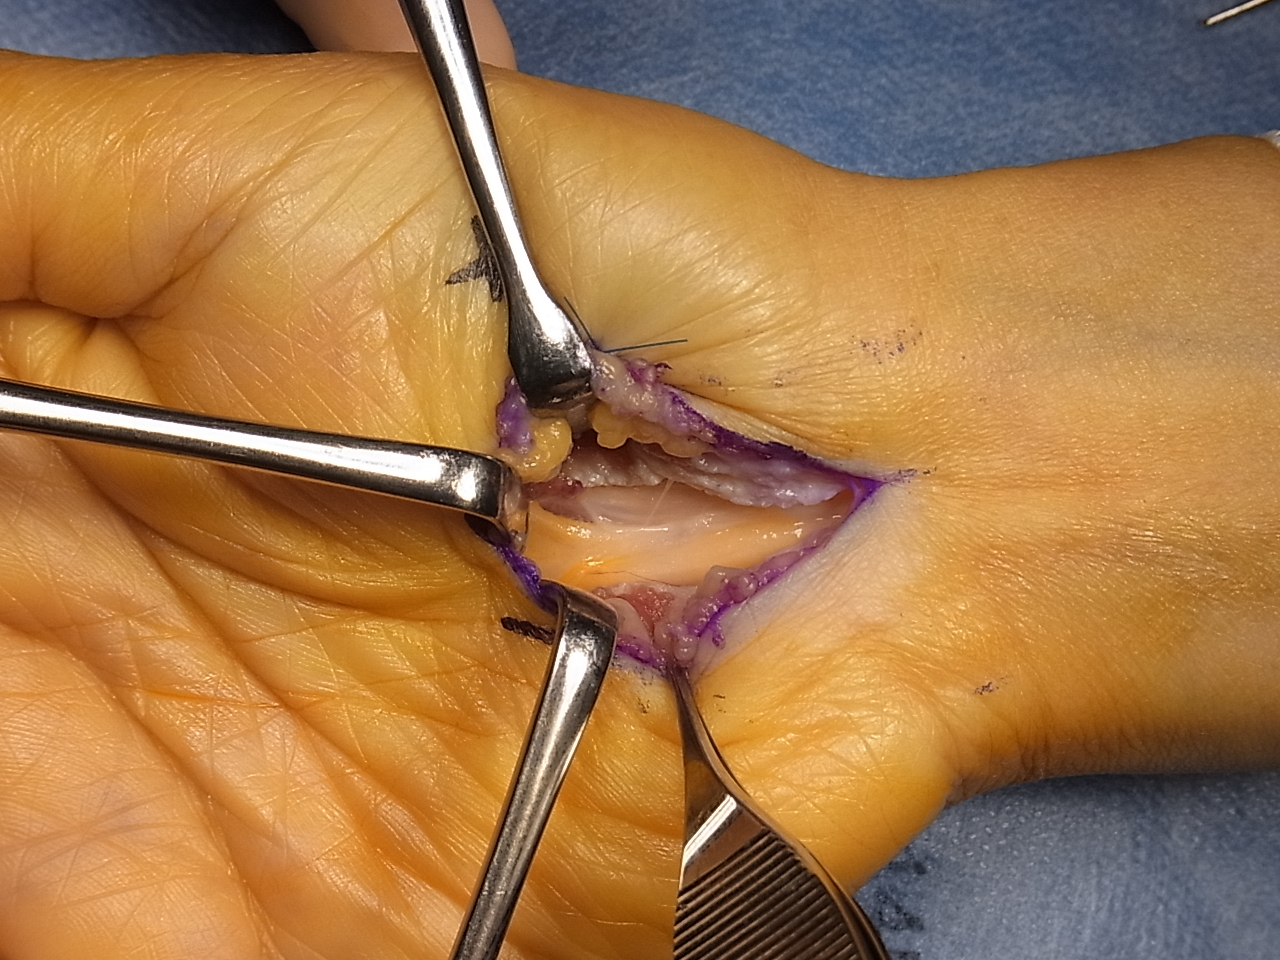

(1) 수술 방법

- 수근관 절개술 : 손목의 수근관을 절개하여 정중신경의 압박을 해소하는 방법입니다. 이 수술은 일반적으로 국소 마취 하에 시행됩니다.